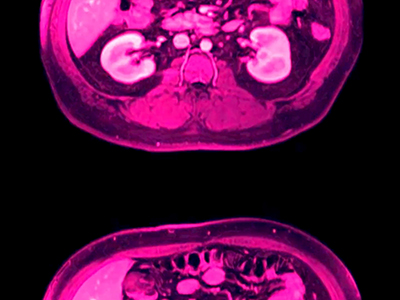

The images pictured at right are a sampling of those submitted with Anna's application.

application artwork (film still)